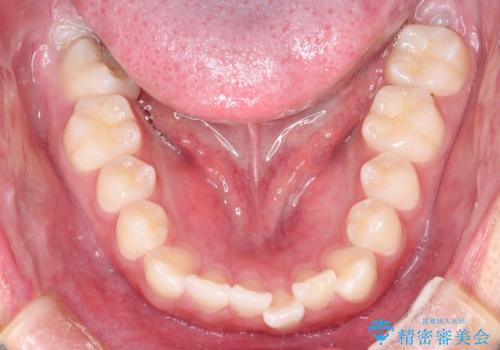

- 前歯のがたつきを主訴に来院されました。

上顎の前から2番目の歯の噛み合わせが反対になっていました。

抜歯矯正も考えられるケースでしたが、非抜歯での矯正を希望され、インビザラインにて治療することとなりました。